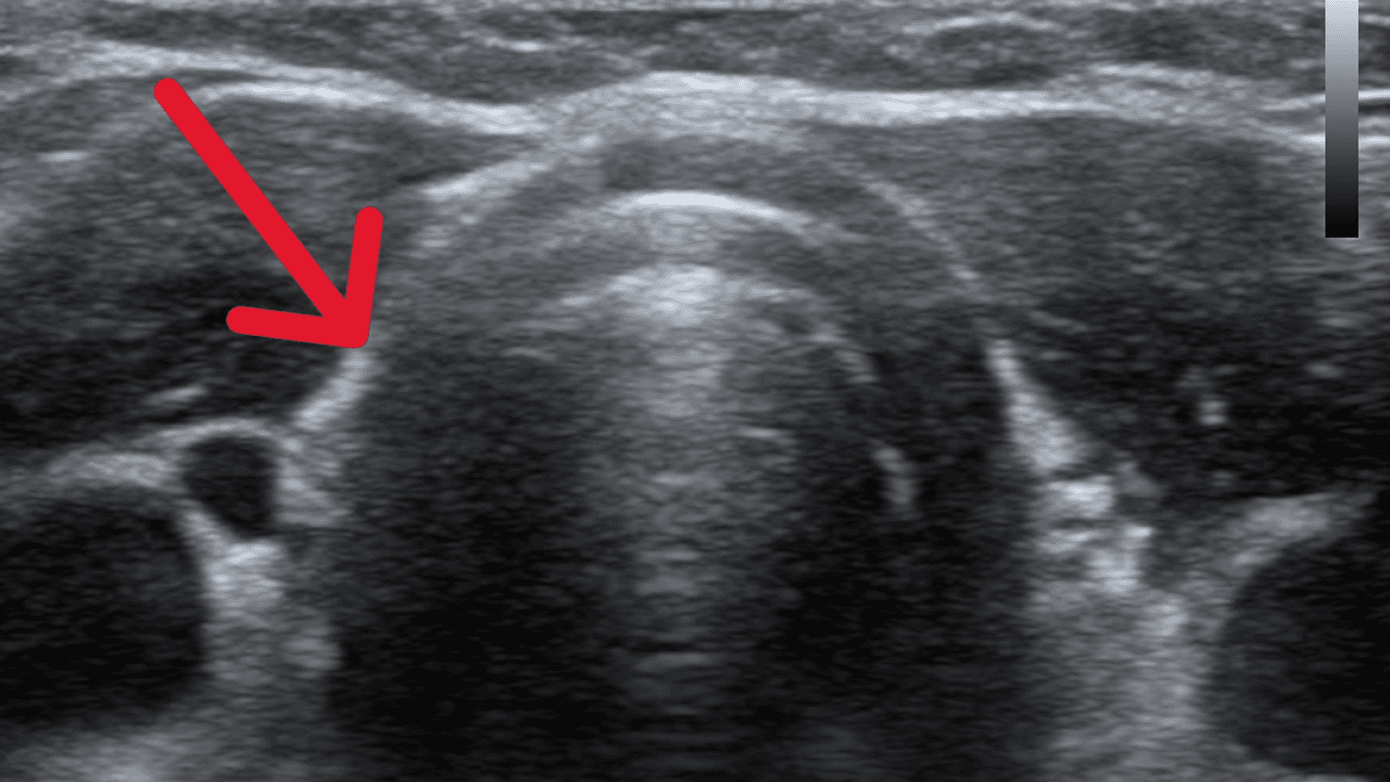

En dobbeltsidig rinoskopi og initial inspektion af cavum oris viste normale forhold. Ved fiberlayngoskopi observeredes en prominerende, velafgrænset, let asymmetrisk tumor ved tungebasis (Figur 1A). Efterfølgende sås, at tumor akkurat kunne visualiseres transoralt ved kraftig depression af tungen. En UL-skanning af halsen viste et tomt thyroidealeje, på hvilken baggrund man fik mistanke om, at det drejede sig om lingval thyroidea (Figur 1 B). Arbejdsdiagnosen bekræftedes ved en 99mTc-pertechnetat-scintigrafi, hvorpå der sås en solitær diffust opladende proces i tungebasis (Figur 1C). Paraklinisk var patienten eutyroid (normale niveauer af thyroideastimulerende hormon (TSH), T3, og T4). En thyroglobulinantistoftest var positiv, mens de øvrige thyroideaantistoffer (TPO og TRAB) var negative. Søvnmonitorering viste enkelte apnøer, uden desaturationer og et apnø-hypopnø-index på 2,5, hvilket er i normalområdet.

Den sande prævalens af lingval thyroidea er ukendt, idet tilstanden ofte er symptomfattig og kan forblive uerkendt. Lingval thyroidea forekommer 4-5 gange hyppigere hos kvinder end hos mænd. De typiske symptomer er bl.a. globulusfornemmelse, åndenød, hoste, synkebesvær, hæshed, snorken, apnø eller blødning. Patienten i sygehistorien havde få symptomer, som havde givet anledning til at opsøge en øre-næse-hals-læge. Tilstanden skal mistænkes ved fund af tumor ved tungebasis og fravær af glandula thyreoidea ved UL-skanning. Diagnosen bekræftes ved scintigrafi, som desuden kan afklare, om der er eventuelt yderligere aberrant thyreoideavæv [3]. Omkring 70% af patienterne udvikler over tid myksødem [4].